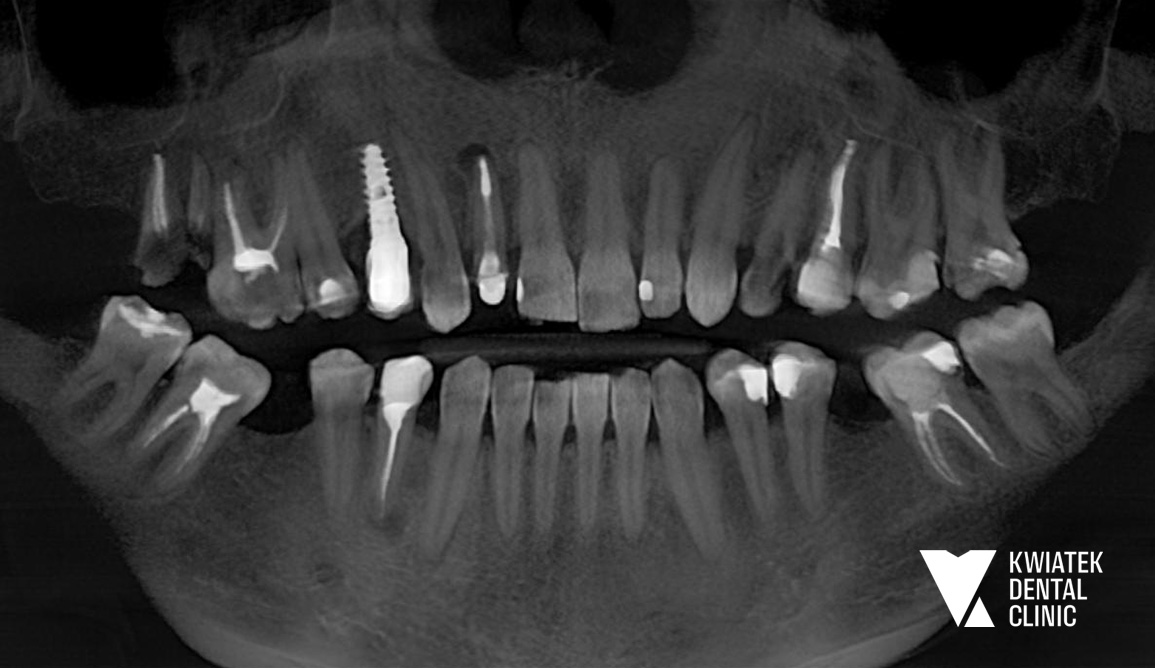

Pierwsze etapy leczenia ujawniły złożony obraz kliniczny:

Diagnostyka była prowadzona etapowo z wykorzystaniem tomografii CBCT, skanów wewnątrzustnych oraz dokumentacji radiologicznej i fotograficznej, co pozwoliło na precyzyjne planowanie leczenia w perspektywie długoterminowej.

Rozpoczęto od zabiegów chirurgicznych i usunięcia zębów niekwalifikujących się do leczenia. Następnie wdrożono zaawansowane procedury implantologiczne, w tym natychmiastowe implantacje oraz zabiegi augmentacji kości z użyciem biomateriałów.